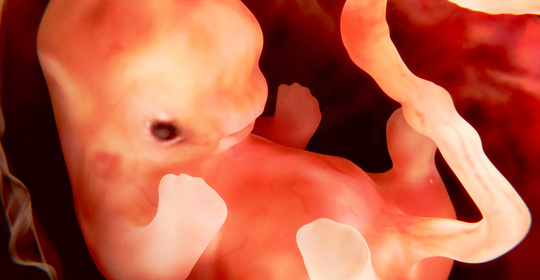

胎兒水腫:瞭解成因、預防與治療方法,守護母嬰健康

胎兒酒精症侯群:瞭解成因、預防與治療方法,守護母嬰健康